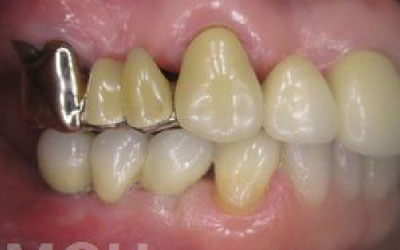

ブリッジとインプラントでは、周囲の歯に与える影響に大きな違いがあります。ブリッジの場合、健康な歯を大きく削る必要があり、さらに通常よりも約1.5倍の咬合力がかかるため、支えとなる歯の寿命が短くなりがちです。実際に、支台歯の約68%が10年以内に抜歯に至るという統計もあります。

ブリッジ治療では、失われた歯の役割を両隣の歯が補うことになるため、その支えの歯には通常の1.5〜2倍ほどの力がかかるとされています。

ブリッジ治療では、欠損部分の両側にある歯を大きく削らなければならず、場合によっては虫歯がなくても歯の神経を抜くことがあります。神経を抜いた歯に被せ物をすると、その歯は急速に弱くなり、寿命が短くなるリスクが高まります。

残っている歯にとって、ブリッジ治療は非常にリスクが高い方法です。

その理由は、ブリッジを作るために隣接する歯を大きく削らなければならないからです。

場合によっては、その歯の神経を取ることもあります。それだけ歯に負担をかけるため、歯の寿命が急激に縮んでしまいます。

最も大きな違いは、前後の歯の寿命に影響が出ることです。

ブリッジの場合、抜けた歯の前後にある歯を、重度の虫歯と同じくらいまで削る必要があります。

また、抜けた歯の代わりに前後の歯が力を支えるため、その歯に常に1.5倍の負荷がかかります。

2)歯を大きく削る+支えの歯に1.5倍の力がかかる

3)前後の歯の寿命が著しく減る

ブリッジの支えの歯は、データでは10年以内に68%が抜歯になります。